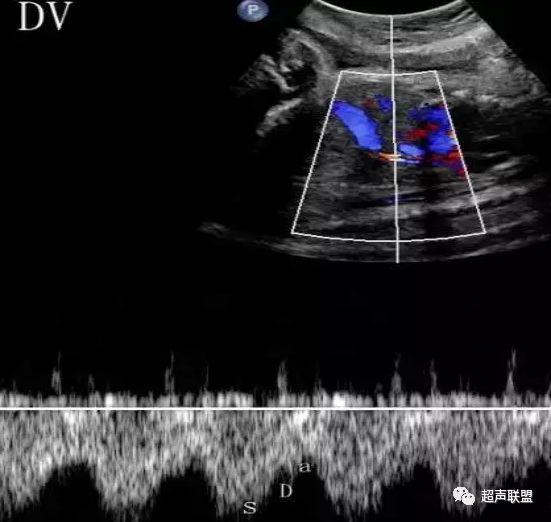

3 胎儿静脉导管

当右心负荷增大,心功能失代偿时,静脉回流受阻,静脉导管a波收缩期流速下降,血流消失甚至倒置。

5、静脉导管:a波消失或反向(见于严重的胎儿宫内缺氧);

7、宫内缺氧时肾动脉及腹主动脉的血流频谱为舒张末期血流的降低,RI及PI值会逐渐升高,若血流再分配严重时其舒张末期的血流将会消失甚至出现反向血流的产生。同时静脉导管也会反映缺氧时心脏功能的情况,当胎儿右心负荷增大,心脏功能失代偿时,静脉回流将会受阻,静脉导管心房收缩期流速逐渐下降,其血流消失甚至于血流倒置。

3、静脉导管a波反向或消失;

图5 胎儿宫内正常静脉导管

图6 胎儿宫内缺氧时静脉导管a波反向